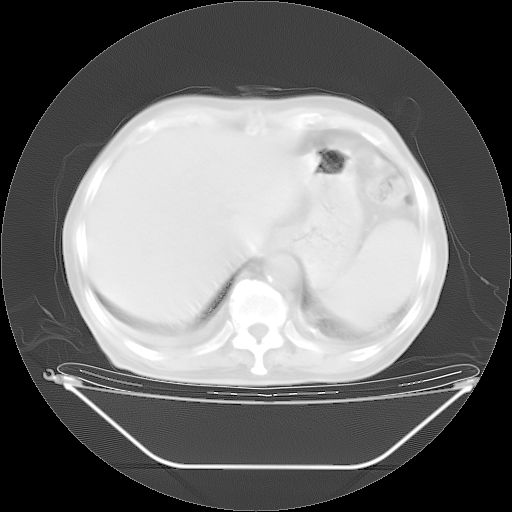

胸腹部CT,诊断意见:左上肺叶钙化灶、左侧胸膜局限性增厚并钙化、胆囊炎。描述部分肺组织呈磨玻璃样改变。

今天复查肺部CT,发现双肺广泛磨玻璃样改变。所以我把3月19日和5月9日相隔50天的肺部CT上传。请大家会诊。

5月9日肺部CT(在4月27日齐鲁医院肺部CT描述部分肺组织磨玻璃样改变,12天后肺组织广泛磨玻璃样改变)